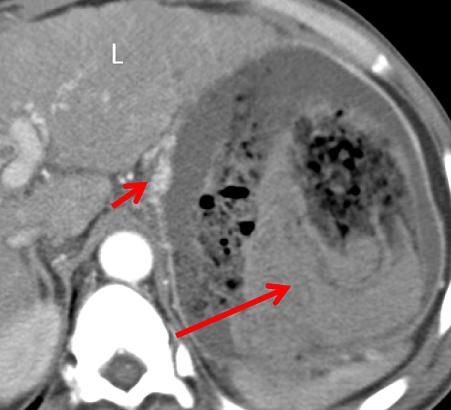

气肿性胃炎是一种罕见的发生于胃部的致命性疾病,临床上以胃壁内出现游离气体为主要特征。 病因包括感染、缺血、药物及特发性等,常见的病原菌包括链球菌、大肠杆菌、金葡菌等。 易感因素包括免疫力低下(如糖尿病及恶性肿瘤患者)、既往有胃黏膜损伤病史(如酗酒、服用 NSAIDs)等。 患者多以急性腹痛、发热、恶心甚至消化道出血为主要表现。

CT 表现为:胃壁增厚及粘膜下水肿,胃壁内积气,这些气体可进入门脉系统致门脉系统积气。

中年男性,突发恶心、呕吐。CT 增强门脉期示胃体部胃壁稍增厚,增厚的胃壁内可见散在气体,另外肠系膜静脉积气。